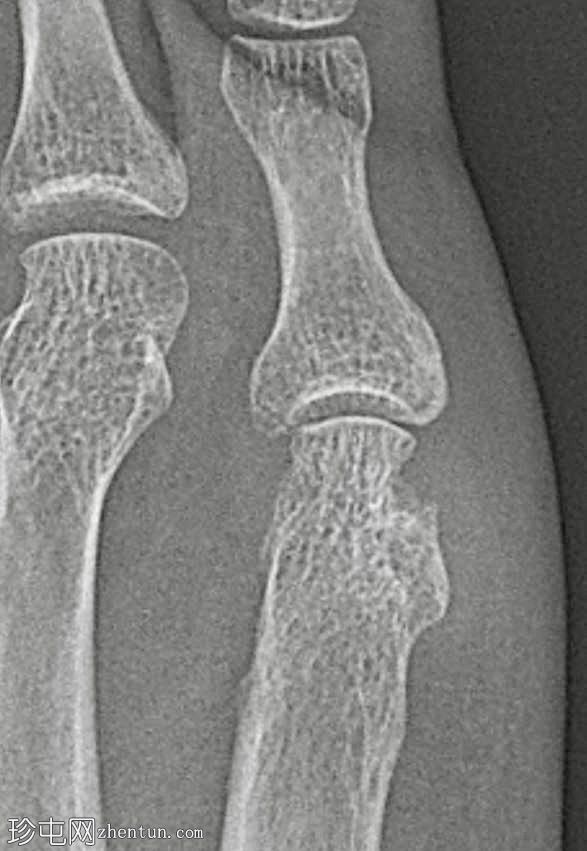

放大锐化图像

骨质疏松伴皮质变薄

左侧(正位、斜位)和右侧(正位斜位)第五跖骨头关节旁骨侵蚀

边界不清

局部软组织肿胀